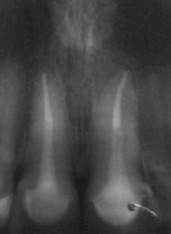

Sobre los términos raíz y corona clínica, quiero

aclarar que la primera se extiende desde apical hasta la cresta ósea y la corona

clínica, desde la cresta ósea hasta oclusal o incisal (Fig. 9) (27), es decir,

que corona clínica no es sólo “lo que vemos clínicamente”, y por tanto

sólo la podemos ver y medir en una radiografía.